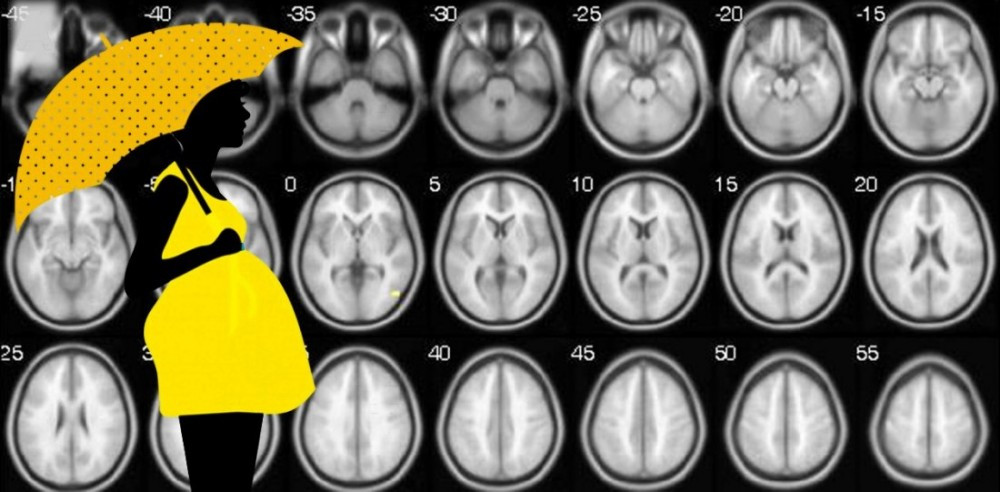

Ученые проанализировали структуру мозга женщин среднего возраста и выяснили, что у рожавших он выглядит моложе, чем у никогда не имевших детей. Это связано с тем, что защитные механизмы, включающиеся в организме будущей матери, действуют в течение всей жизни. Результаты исследования опубликованы в журнале Proceedings of the National Academy of Sciences.

Группа европейских ученых из Великобритании, Норвегии и Нидерландов решила проверить эту гипотезу. Они изучили структуру мозга у 12021 британских женщин в возрасте 54-55 лет (9568 из них рожали хоть раз в жизни, а 2453 не рожали ни разу). Используя методы машинного обучения, исследователи создали алгоритм нейровизуализации, позволяющий не только обнаружить в мозге женщины следы изменений, заложенных в период беременности, но и определить, сколько было родов.

Анализ показал, что мозг рожавших выглядел моложе. Биологический возраст их мозга был на 2-3 года меньше, чем у нерожавших сверстниц. Причем, чем чаще рожала женщина, тем больше был разрыв между реальным и биологическим возрастом ее мозга.